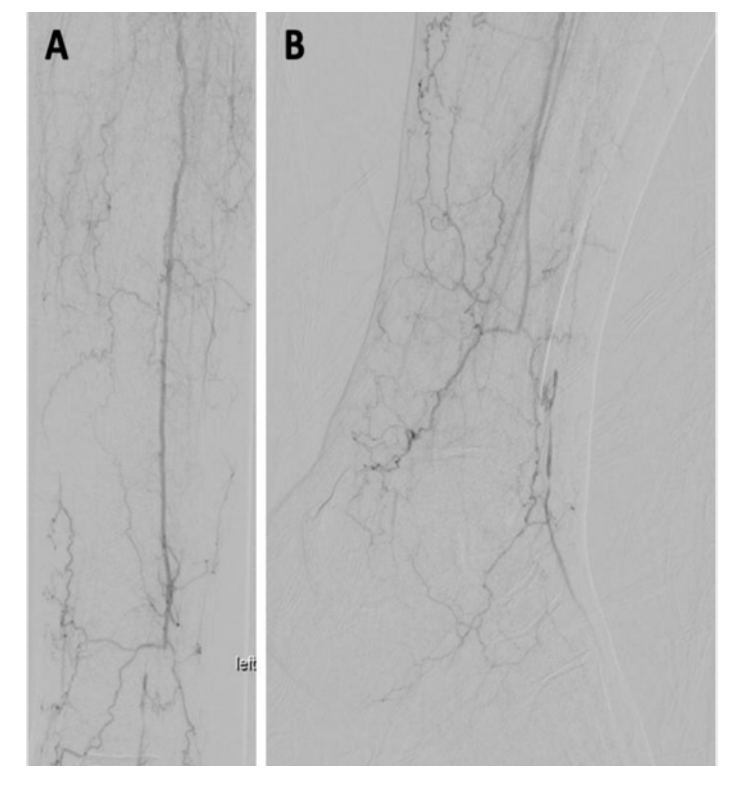

The repeat angiogram demonstrated restoration of flow throughout the femoropopliteal segment, with direct inline flow to the peroneal artery (Figure 4). On this study, distal peroneal artery collaterals and perforators were seen reconstituting pedal arteries, not demonstrated previously, in keeping with the patient’s markedly improved physical exam. There was near resolution of the previously identified superficial femoral arteriovenous fistula. Despite the slightly ectatic appearance of the distal popliteal artery and tibioperoneal trunk, no true aneurysmal dilation was identified on the recent CTA. An approximate 80% stenosis was present within the tibioperoneal trunk, at the same location where difficulty was encountered in advancing the wire on the previous day. Angioplasty of this segment was performed with a 3.0 x 60 mm balloon in order to improve single-vessel inline flow to the foot.

Following angioplasty, the repeat angiogram demonstrated resolution of the tibioperoneal stenosis, but with a new, nearly occlusive 5 mm filling defect in the proximal peroneal artery (Figure 5). Several therapeutic options were discussed and a decision to perform spot laser thrombolysis was made. Using a 0.9 mm Turbo-Elite laser atherectomy catheter (Philips), a total of two passes were performed across the proximal peroneal artery at low and moderate fluence and rate settings. The repeat angiogram demonstrated unsuccessful lysis, with the embolus now having migrated into the mid segment of the peroneal artery, resulting in complete occlusion. Fortunately, an .014-inch wire remained across the occlusion and a decision to perform long-segment angioplasty in order to macerate the lesion was made. The angioplasty was performed with slow and prolonged inflation of a 2.0 x 220 mm balloon, with the balloon tip in the distal peroneal artery. It also resulted in more distal migration of an occlusive filling defect, bringing complete occlusion of important, unnamed collaterals to the pedal arteries, as well as the perforating branch of the peroneal artery.